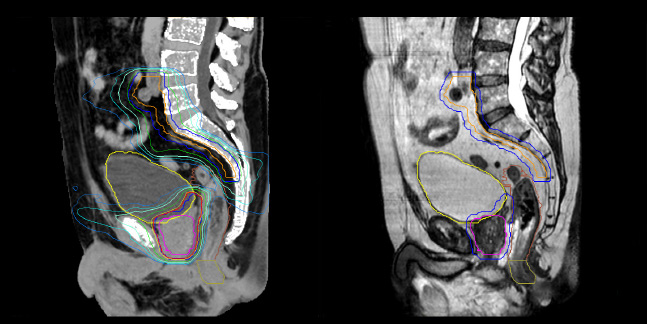

Prostate MR-only radiotherapy planning with use of rectal spacer

Hôpital de La Tour uses an implanted rectal spacer (SpaceOAR®, Boston Scientific) for patients receiving prostate radiotherapy to provide space between the rectum and prostate. 3D T2W TSE MRI provides excellent rectal spacer visualization and is used for OAR and target contouring. The dose plan is calculated on the MRCAT dataset.

Simulation imaging

Tranversal 3D T2W TSE with Compressed SENSE, acquired on Ingenia MR-RT 1.5T (left).

On-console generated MRCAT (right).

MR-based contouring and planning

MRCAT is primary image dataset for dose calculation (left).

3D T2W TSE MRI with 36 cm Field-of-View is used for delineation of prostate and organs at risk (right).